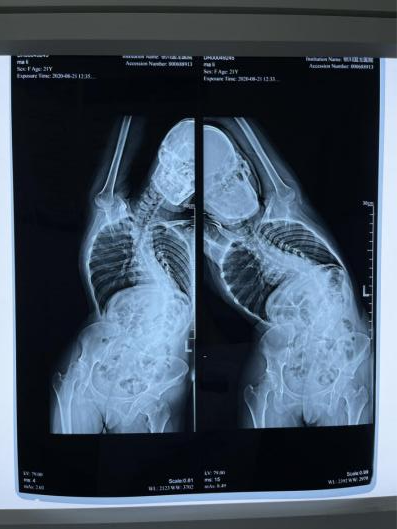

22岁,本该是花朵一般的最美年华,却因为严重的脊柱弯曲造成背部畸形

脊柱畸形